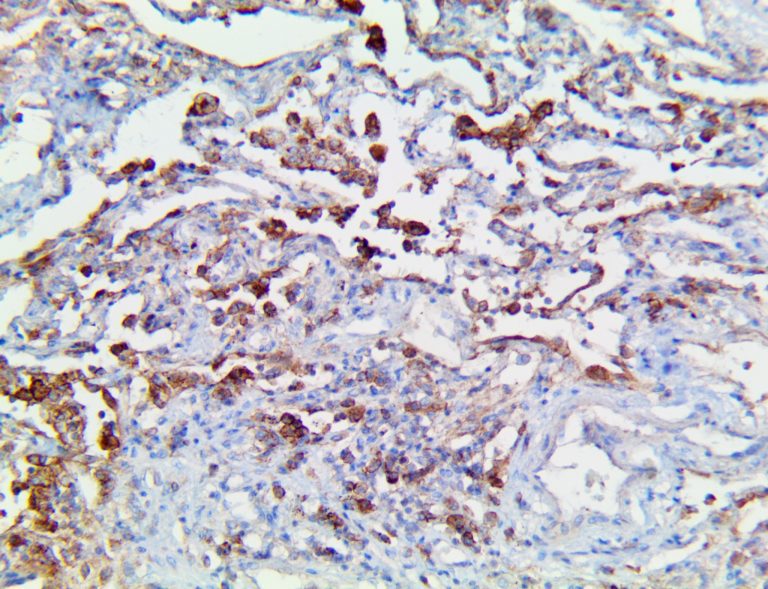

This activation induces inflammatory monocytes to highly express IL-6, starting a localized and then systemic cascade effect that results in hyperproduction of IL-6, which accelerates the inflammatory process. Because IL-6 also increases vascular permeability, excessive levels cause blood vessels to become very leaky. This, along with clotting factors released from vascular endothelial cells, stimulates the coagulation cascade, resulting in microthrombosis (tiny clots), which leads to ischemia and tissue death of the kidney, intestines, heart, liver, brain and extremities.